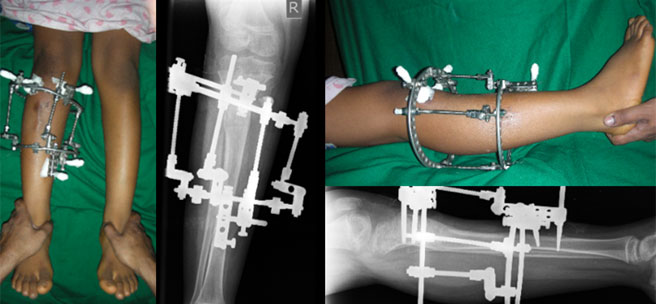

| The x-ray and clinical appearance after full correction. The right leg looks similar to the left one in appearance. On x-ray the axis is well corrected. |